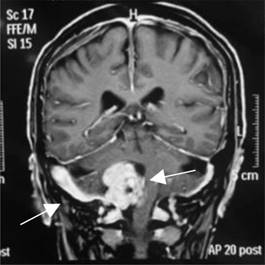

Se realiza resonancia magnética de cráneo debido a la sintomatología antes mencionada; reporta un schwannoma de localización intra y extracraneal (Figuras 1 y 2).

El estudio de elección para diagnosticar los schwannomas es la resonancia magnética, siendo la prueba de mayor definición. En este caso, encontramos afectado el bulbo raquídeo que contiene estructuras como el centro cardiorrespiratorio, los nervios glosofaríngeo y vestibulococlear y el centro de deglución; el efecto de masa explica los síntomas de hipoacusia sensorial ipsilateral y disfagia por la abolición del reflejo de deglución. Otra estructura afectada es el centro cardiorrespiratorio, que al estar siendo comprimido resulta en un estado de acidosis respiratoria crónica.

Las estructuras involucradas neurológicamente en el paciente, llevan a un cuadro clínico confuso, ya que la masa tiene una localización intra y extracraneal, algo poco frecuente en los schwannomas.